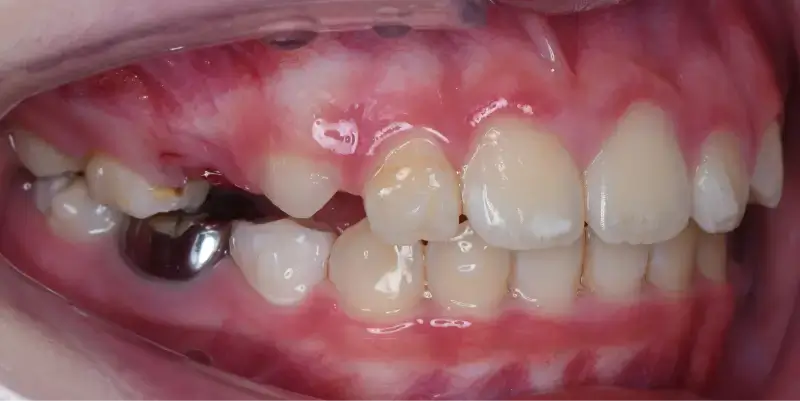

兒童早期矯正,又稱為「預防性矯正」或「第一階段矯正」,指的是在孩子乳牙或混合牙期(約7~10歲)時,就針對牙齒排列、咬合不正、牙弓發育等問題提前介入的矯正治療。 目的不只是「把牙齒排整齊」,更重要的是引導上下顎正常發育,減少未來拔牙、正顎手術的機率,讓恆牙有足夠空間健康萌發。

預防臉型歪斜與大小臉

如單側咬合、下巴偏斜等問題,若不及時矯正,將可能導致骨性歪斜,進一步需要正顎手術。

相當於國小低至中年級,這時會開始進到乳牙換成恆牙的階段,也是牙齒移動速度快的時期,在這個階段接受矯正能夠擁有良好的矯正效率,因此也被定義為「兒童矯正的黃金期」。

早期矯正屬於「第一階段」,目的是為了改善結構性問題與預防性治療,等恆牙長齊後,或許可能需要第二階段矯正做細部微調,但相較從未矯正過的孩子,已做早期矯正的小朋友通常不需拔牙、減少正顎手術的風險,而且療程也會更短。